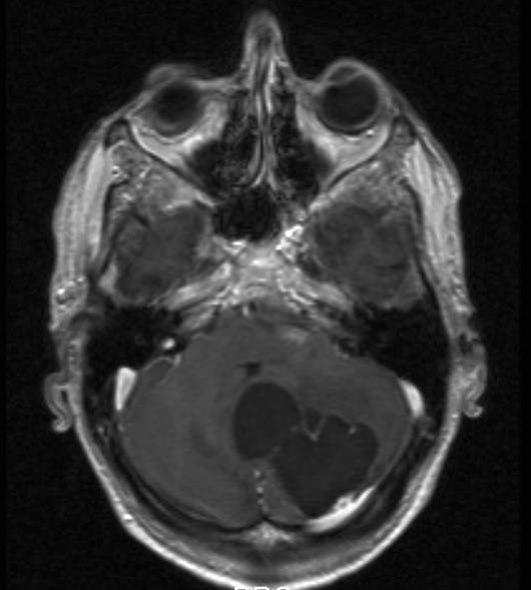

Hemangioblastom, aksialt snitt

Gjengitt med tillatelse av Radiologisk avdeling, Universitetssykehuset Nord-Norge